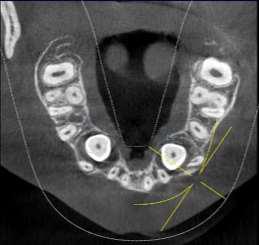

CORTES AXIALES

Con la evaluación de la tomografía volumétrica en cortes axiales y transversales se observa la expansión y adelgazamiento de la tabla ósea vestibular y palatina legando a dicha pérdida ósea, también se observa el desplazamiento de la pieza 1 3 la cual se encuentra retenida y desplazada hacia la basal vestibular.

En el corte tomográfico oblicuo–sagital derecho se observa: (figura 3)

Imagen hipodensa, bien delimitada, de contorno redondeado, ubicada en el seno maxilar derecho.

La lesión parece originarse desde el piso del seno, con íntima relación con los ápices dentarios superiores posteriores.

No se aprecian signos de erosión ósea marcada, aunque existe adelgazamiento del piso sinusal

La densidad es homogénea, lo que orienta hacia un contenido quístico

Seno maxilar derecho: ocupándolo parcialmente, se identifica una imagen hipodensa, bien delimitada, de contorno redondeado y homogéneo, compatible con lesión quística

Produce expansión con adelgazamiento de la pared ósea sin clara evidencia de destrucción.